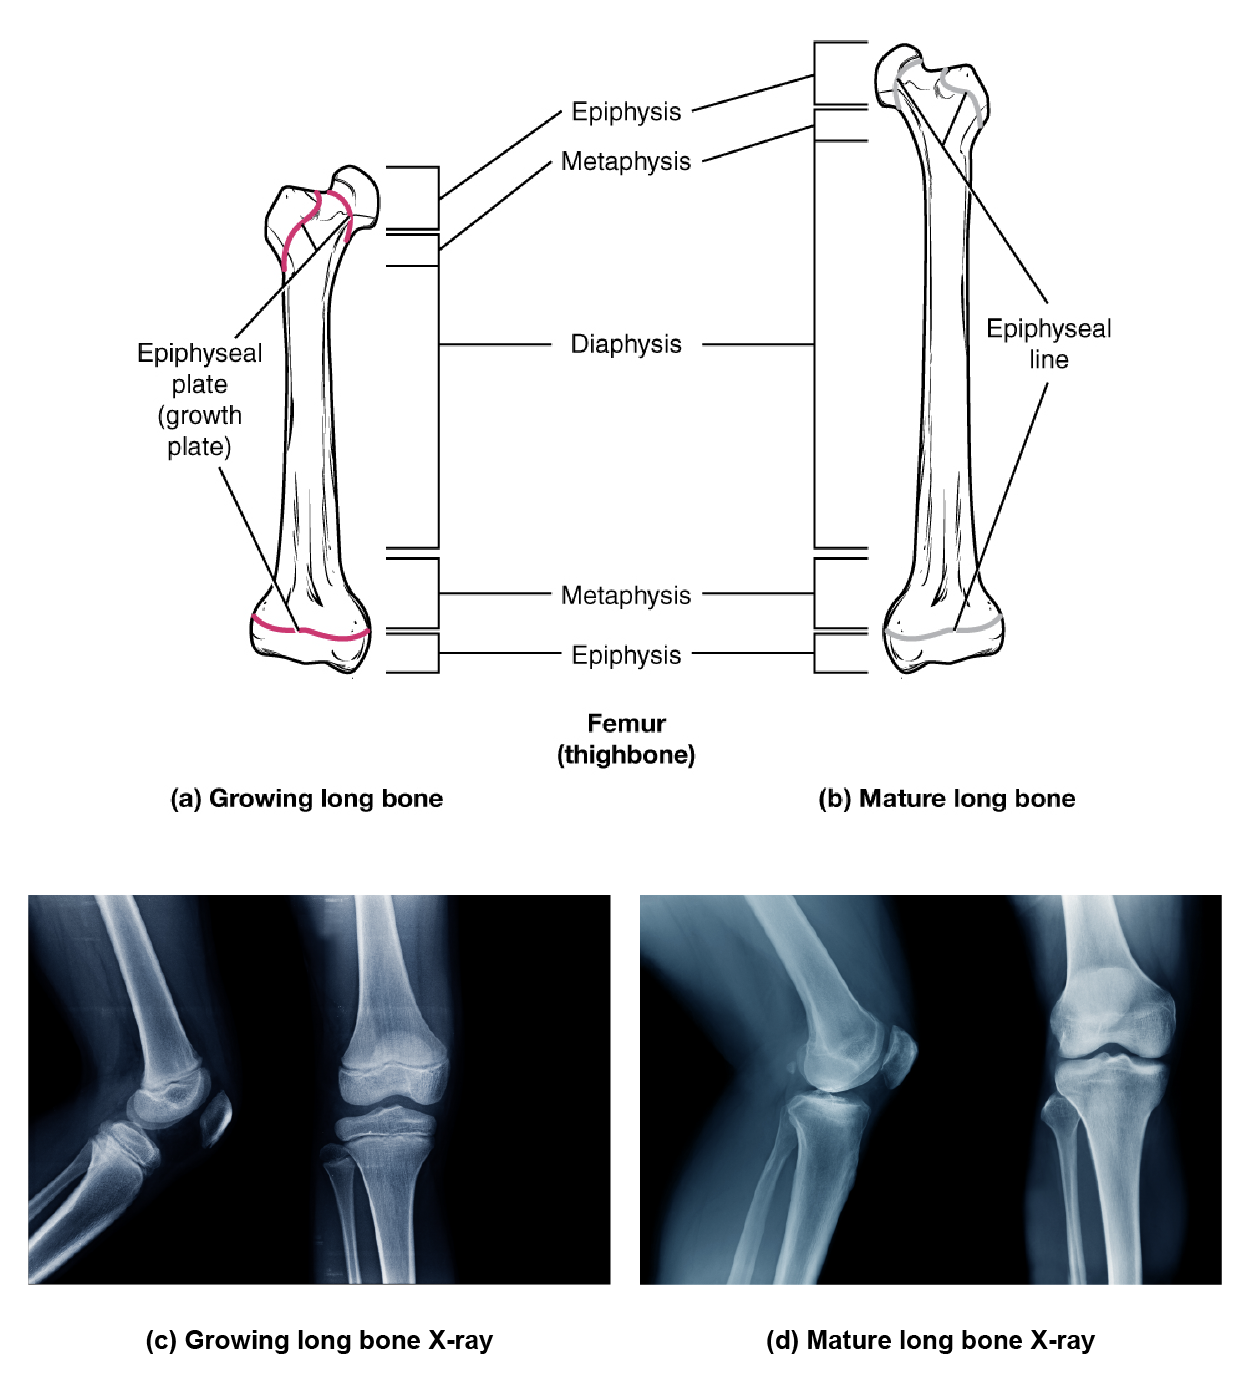

Long bones stop growing at around the age of 18 in females and the age of 21 in males in a process called epiphyseal plate closure. During this process, cartilage cells stop dividing and all of the cartilage is replaced by bone. The epiphyseal plate fades, leaving a structure called the epiphyseal line or epiphyseal remnant, and the epiphysis and diaphysis fuse.

An X-ray of this region shows the presence of an epiphyseal plate or line and can be used to determine whether a bone is done growing or not, as well as its approximate age.

Progression from Epiphyseal Plate to Epiphyseal Line—As a bone matures, the epiphyseal plate progresses to an epiphyseal line. (a) Epiphyseal plates are visible in a growing bone. (b) Epiphyseal lines are the remnants of epiphyseal plates in a mature bone. (c) Epiphyseal plates show up on X-rays as dark gaps in the bone. (d) Epiphyseal lines show up on X-rays as bright bone.